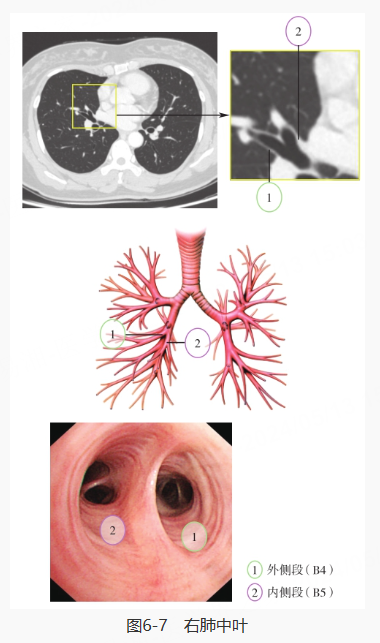

继续探入,先对右肺进行探查,分别是右主支气管、右肺上叶·中间段支气管、右肺上叶、右肺中叶·下叶、右肺中叶、右肺下叶背段和右肺下叶基底段: